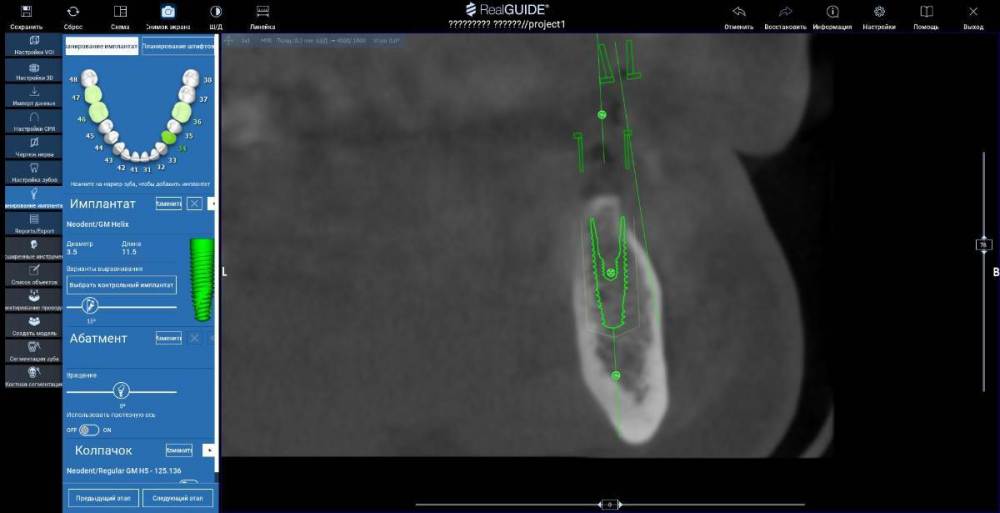

TIGER Опубликовано 10 августа, 2022 Поделиться Опубликовано 10 августа, 2022 Всем привет!Небольшой кейс с расщеплением,прошу обратить внимание на насадки,это не пилы, а остеотомы(скальпели)очень быстрое расщепление без потери тканей!Видео с операции тут 139257348_3.mp4 1 2 Ссылка на комментарий